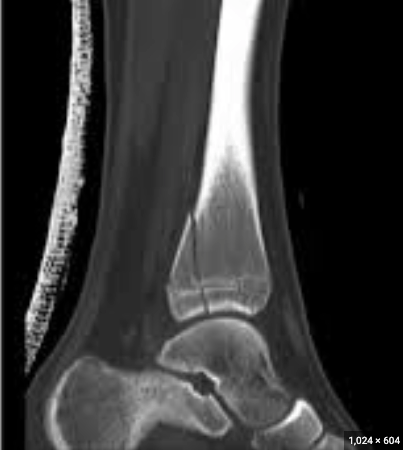

Salter-Harris classification for this fracture.

What is a Salter Harris IV fracture?

The vascular injury that can arise from this injury.

What is a popliteal artery injury?